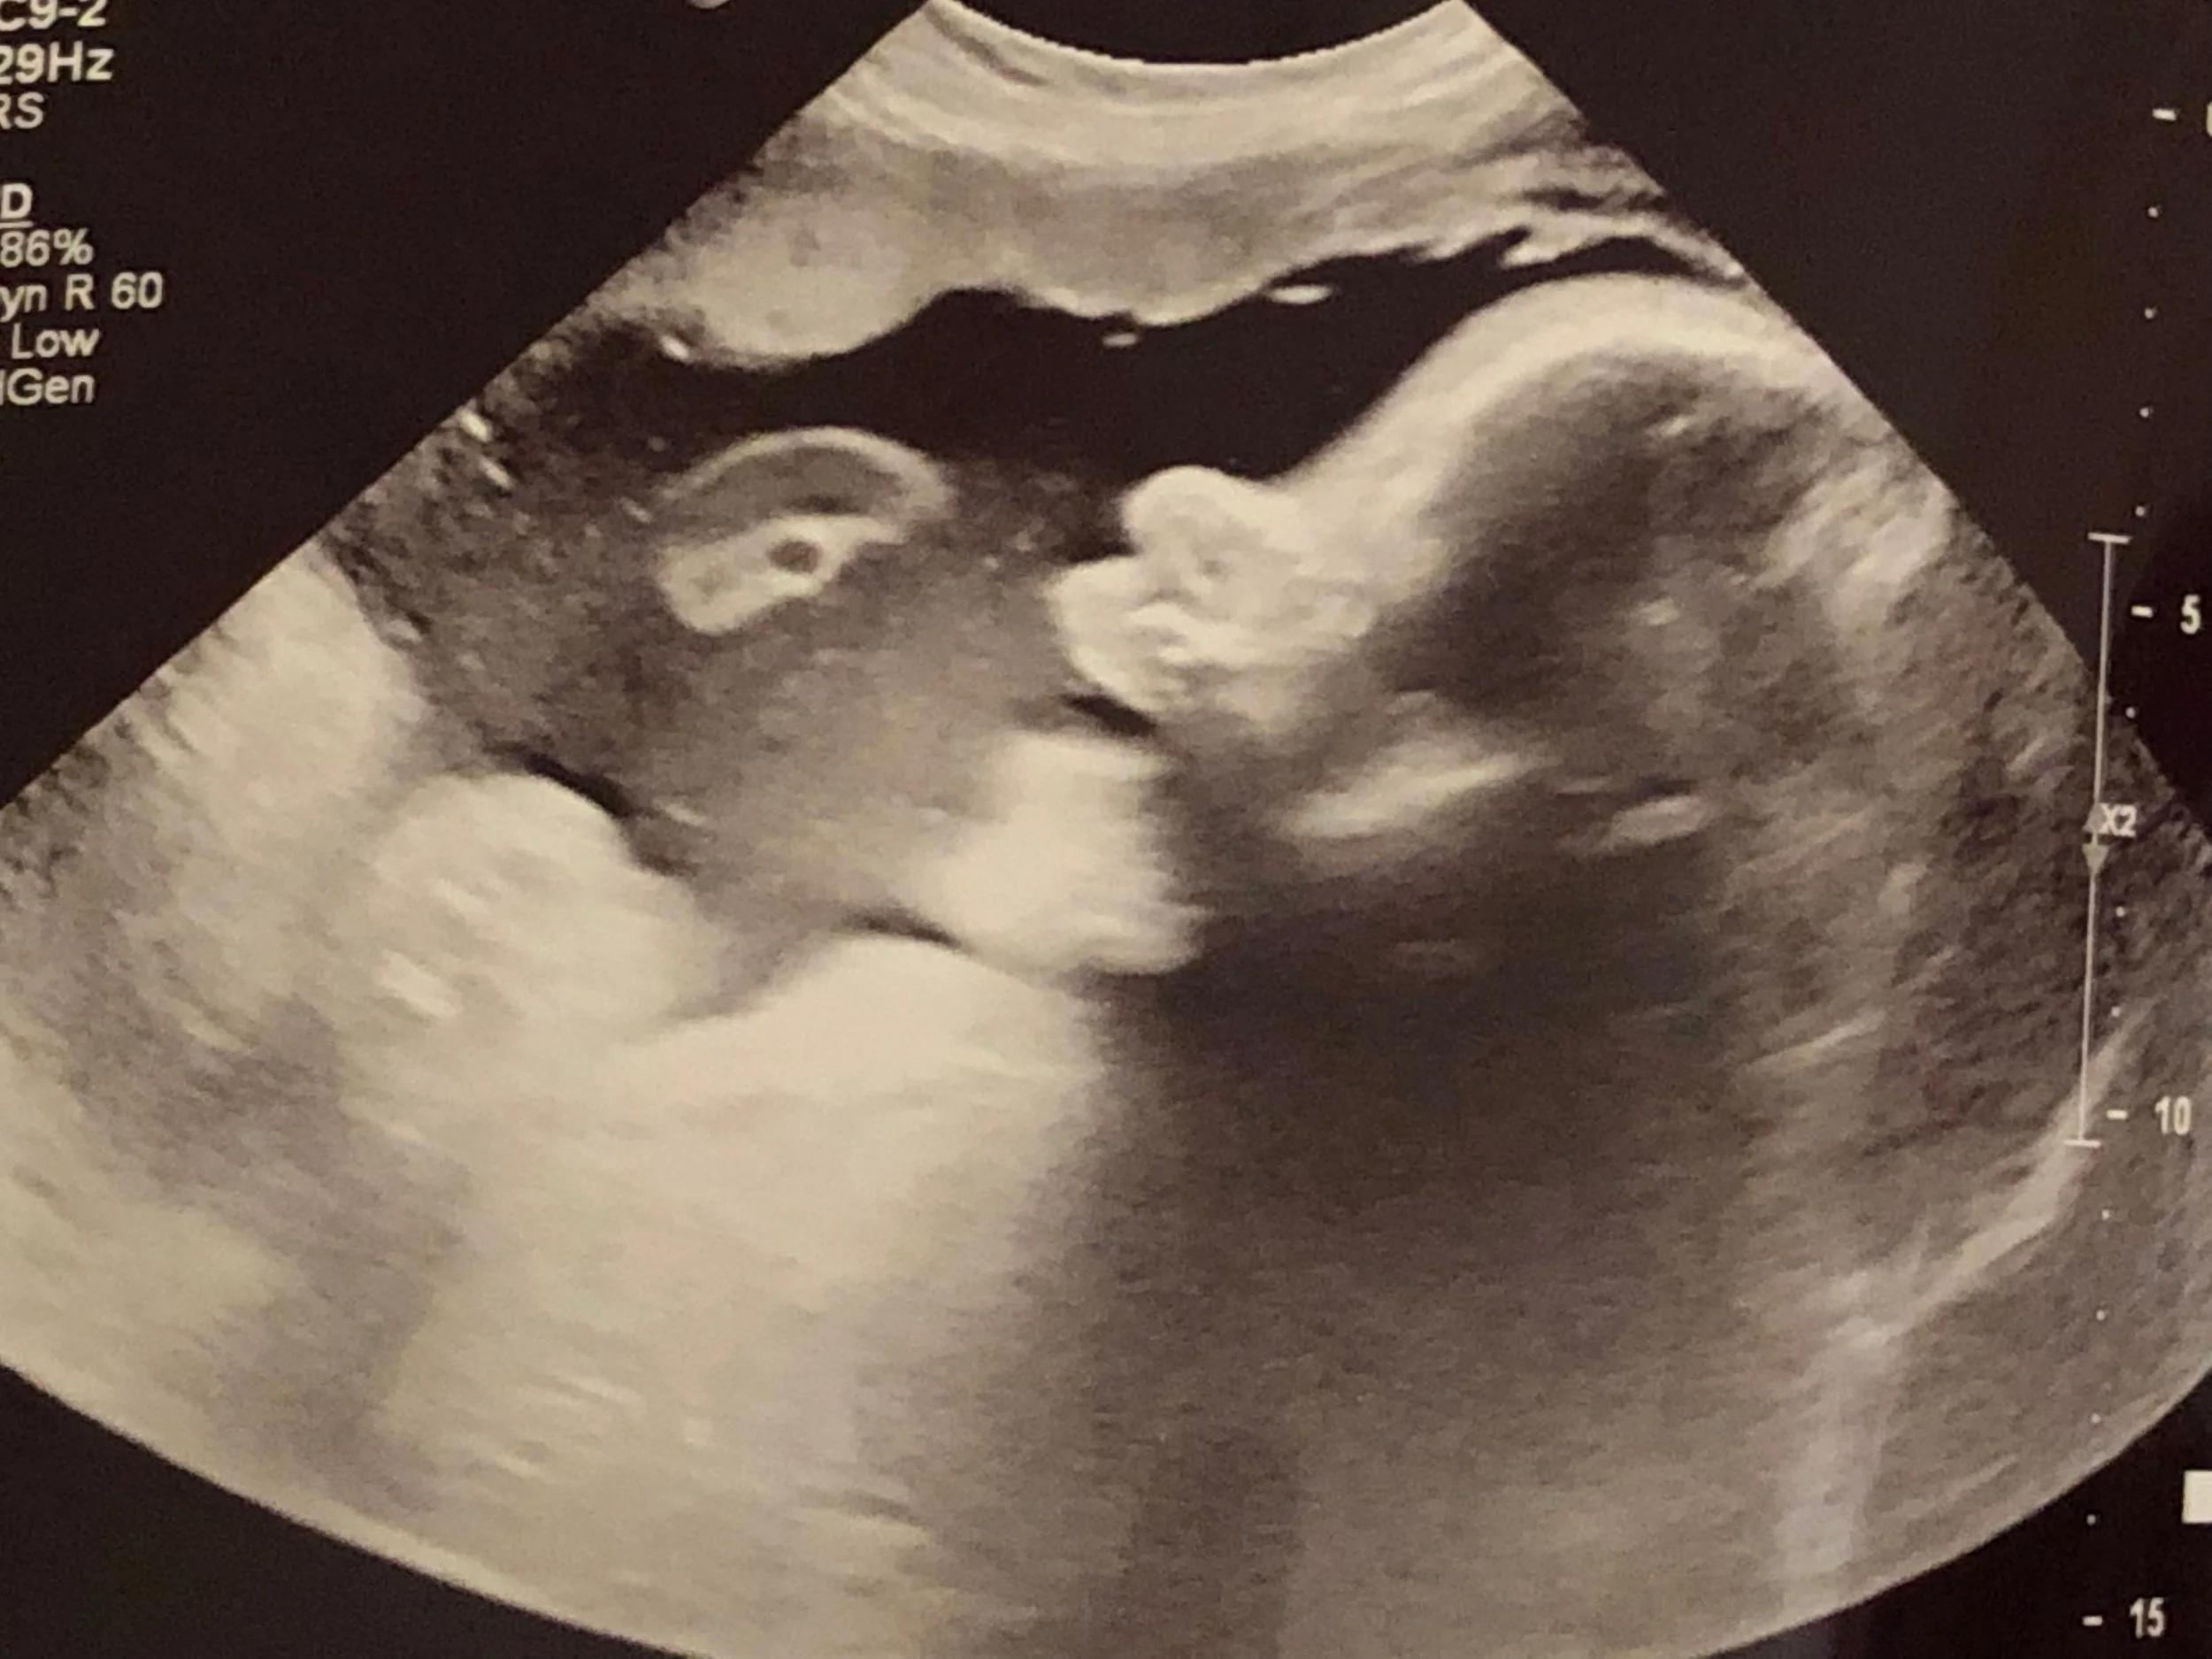

Elijah was born March 29th at 1:20am. I was beyond exhausted and overjoyed as they laid him on my chest. Over his cries though I could hear and feel that something was wrong. I couldn’t tell from my angle but Elijah’s head was not shaped normal. JT immediately asked our midwife to be honest and straightforward with us. She calmly, told us that she had only seen this one other time and it would require surgery. Surgery?! Ha! We are leaving for our overseas mission trip in 8weeks … we don’t have time or money for surgeries! I don’t believe that God has brought us all this way for us to be stopped by surgeries! All of these thoughts were flooding my head. In that moment, we stopped. We laid hands on our son and prayed for God to move his bones. I wish I could remember our exact prayer but to be honest this isn’t about our words. It is about our obedience and faith.

The midwife called the pediatrician to inform him of the condition. It was decided that staff would monitor him and that the DR would be in first thing to exam and get a plan of action together. Elijah was on me for an hour after birth and then we had him go the nursery for a few hours so we could get some rest before his next feeding. Two hours later they brought our son back to us. We removed his stocking cap to see how his head was doing … only to reveal HE WAS HEALED!

When the DR came in around 6am he took a look at Elijah baffled, and asked why he was called in?! I pulled up my phone to show him Elijah’s picture after birth and he said, “That doesn’t make any sense!” Which we responded, “Yes, it does! Our God healed him!” Not only did he confirm but our midwifes and the nurses all were speechless and dumbfounded when they came back to see his head. What an amazing testimony for our son. Elijah was named before he was born but for those who do not know his name means “ My God is Yahweh!” I don’t know why God chose to heal our son but I want to do my best to ensure that HE gets ALL THE GLORY!